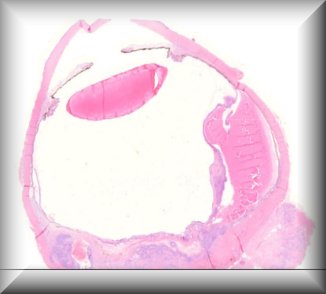

Julia Weller: Corneal edema occurring 45 years after penetrating keratoplasty in a patient with keratoconus |